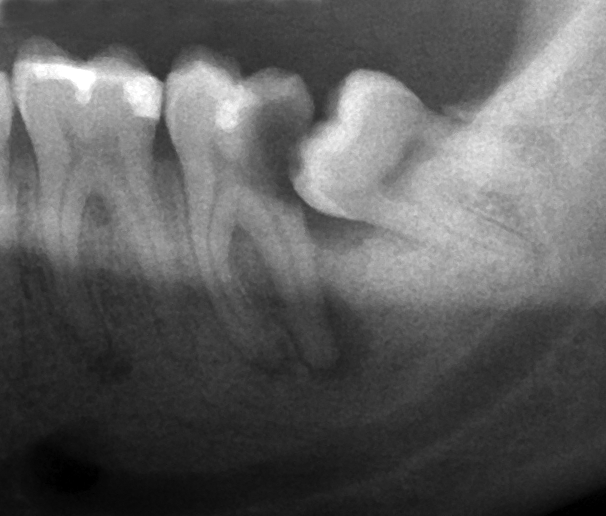

हो, अक्कलदाढेच्या बाबतीत बऱ्याच वेळा बघितलेला प्रॉब्लेम असा की, काही वेळेला अक्कलदाढ वाकडी असते. अशा दाढेमुळे बऱ्याचदा वाकडी अक्कलदाढ आणि त्या अलीकडची दाढ यांच्यामध्ये जेवण अडकतं आणि तिकडे ब्रश व्यवस्थित पोहोचत नसल्यामुळे स्वच्छता राखली जात नाही ; परिणामी कधीकधी अक्कलदाढ तर किडतेच आणि अलीकडची दाढ सुद्धा कीडते. अशा वेळी दोघांची ट्रीटमेंट करावी

लागते ’’

त्यामुळे अशी वाकडी दाढ असेल तर त्रास होण्या आधीच काढलेली बरी…

“हो, अशी अक्कलदाढ काढण्यासाठी बऱ्याचदा स्पेशलिस्ट डेंटिस्टना बोलवावे लागते कारण ही दाढ वाकडी व हाडात अडकलेली असल्यामुळे बाकीच्या दातांप्रमाणे सहज निघू शकत नाही.

हे तज्ञ डेंटिस्ट छोट्याशा प्रोसीजरने ही दाढ काढतात ज्यात दाढेला हाडातून आधी थोडं ढीलं केलं जातं आणि मग काढलं जातं . कधी कधी ह्या प्रोसीजर नंतर हलकी सूज , थोडा तोंड उघडायला त्रास जाणवू शकतो ; पण आपली नेहमीची कामं व्यवस्थित पार पाडता येतात . २ दिवस मऊच खाणे खाणे, दिलेली औषधे व्यवस्थित घेणे ही पथ्ये पाळावी लागतात.